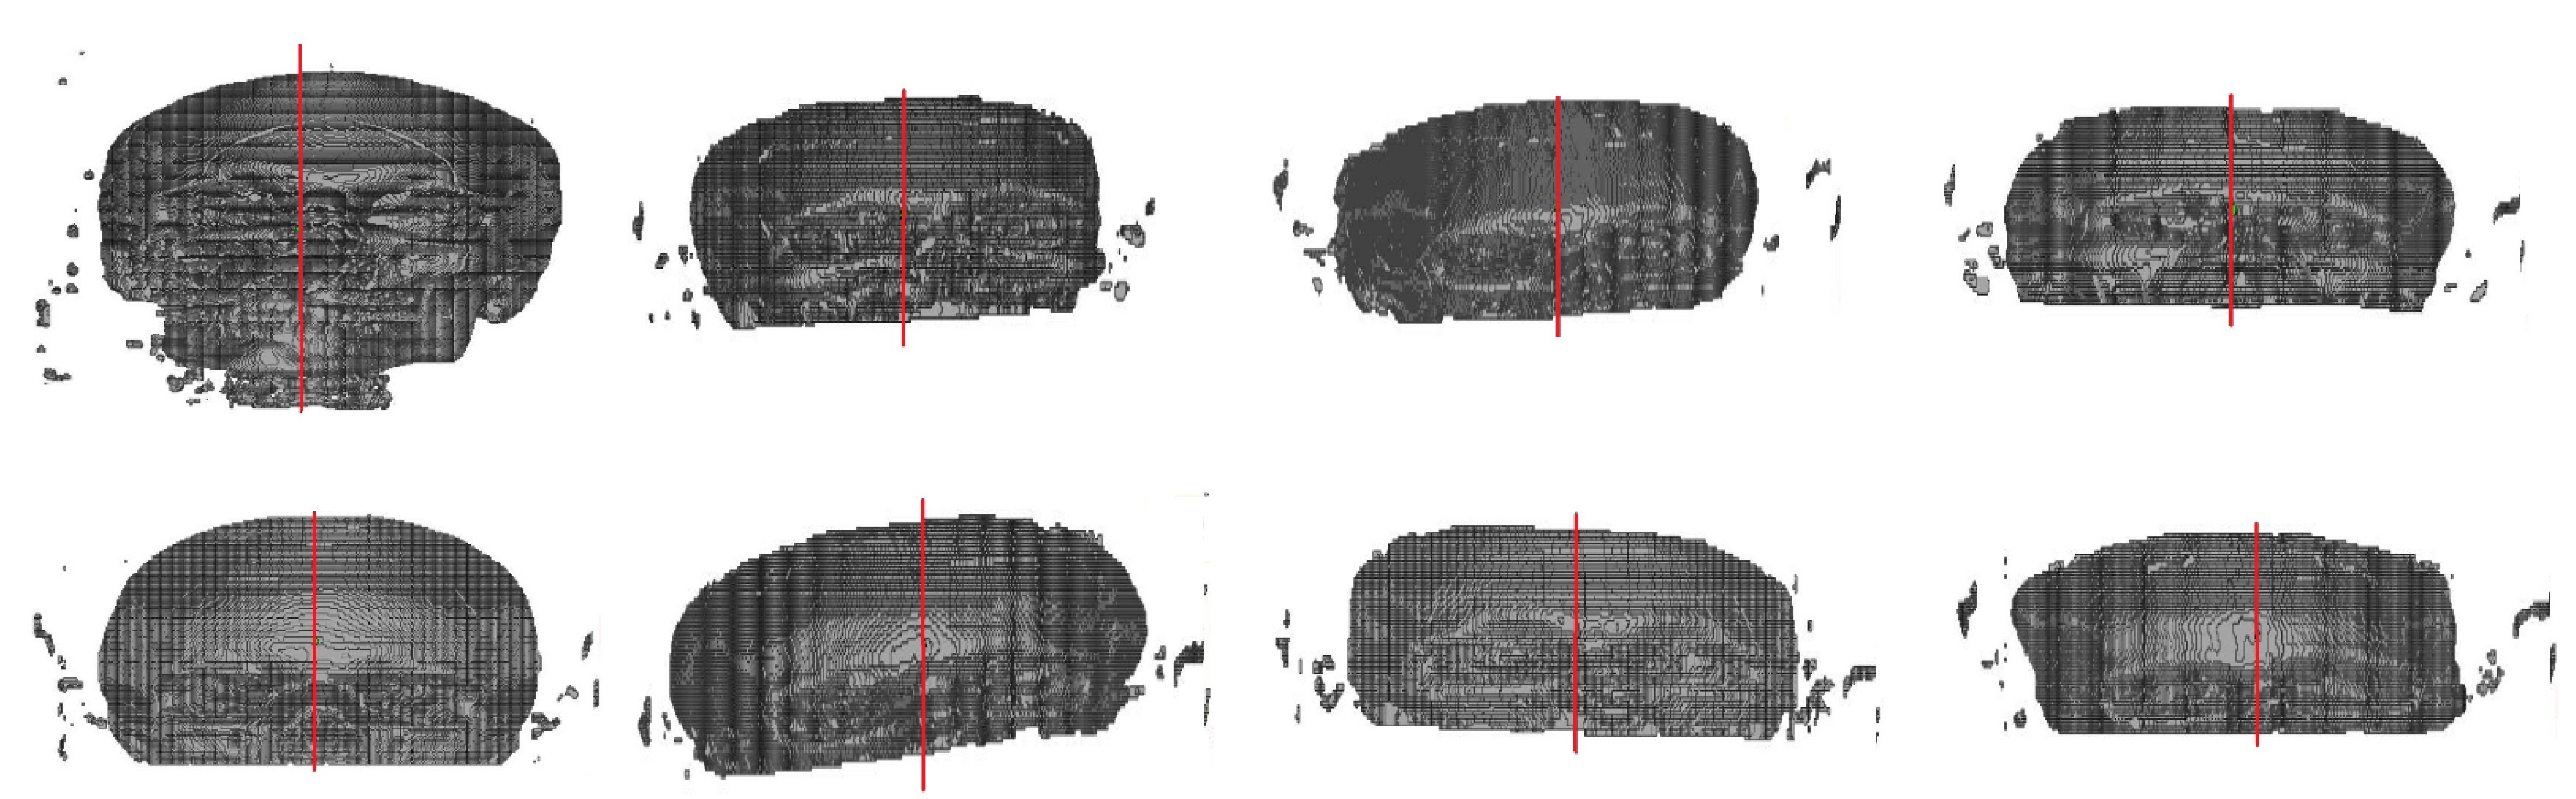

3.4. Deformed Skull Test

- the small database size, which is already reported in [27];

- to the best of our knowledge, there are no deformed CT database available which restricts the possibility to train the system with deformed images;

- during the ground truth segmentation process and voxelization, a few regions of interest (ROIs) may have not been incorporated in the 3D model. The first may be caused by the manual selection of the ROI, performed by an expert, which leads to the CNN generating the defects. Secondly, a quantity of information from the skull voxel may be lost due to the smoothing of the edges and noise residuals removal performed in the segmentation process;

- regarding the center of the 3D images, as reported by [8], when the image suffers from a lack of symmetry, non-uniform brightness, deformation, interference, or incompleteness, the calculation of the image center using geometric moments becomes complex and finds some restrictions as this technique is a quantitative measure of an image’s function or structure.